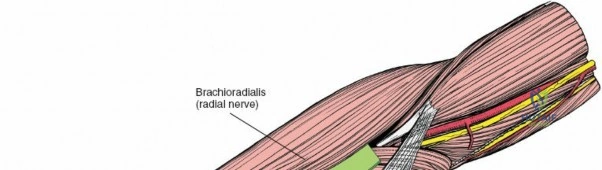

Superficial Surgical Dissection and Internervous Plane

Incise the deep fascia of the forearm in line with the skin incision. The initial goal is to identify the medial border of the brachioradialis as it courses down the forearm. It is a common pitfall to search for this border too far laterally. At the level of the elbow, the brachioradialis is expansive and extends almost halfway across the anterior forearm. It is surprisingly easy to mistake the plane between the brachioradialis and the extensor carpi radialis longus for the correct intermuscular plane.

To confirm the correct plane, look for the superficial branch of the radial nerve. This sensory nerve runs on the undersurface of the brachioradialis muscle. Once the true medial edge of the brachioradialis is found, develop the plane between it and the pronator teres (proximally) or the flexor carpi radialis (distally). Retract the brachioradialis laterally, taking care to keep the superficial radial nerve attached to its undersurface to protect it from traction injury.

The proximal radius is draped by the supinator muscle. The PIN passes directly through the belly of the supinator. To protect the nerve, the forearm must be fully supinated. Supination dynamically rotates the radius, carrying the insertion of the supinator anteriorly and simultaneously displacing the PIN laterally and posteriorly, safely away from the surgical field.